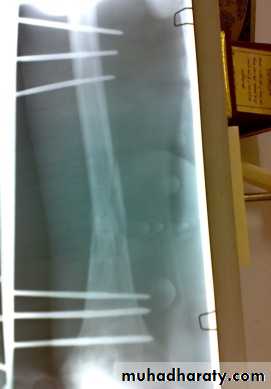

Reduction and holding by traction,( fixed traction, balanced traction with or without splint followed by exercise) rarely applied.

Conservative treatment:

Traction with a splint (Thomas’ splint) is first aid for a patient with a femoral shaft fracture, Shock treatment, and early transport to hospital.Thomas splint